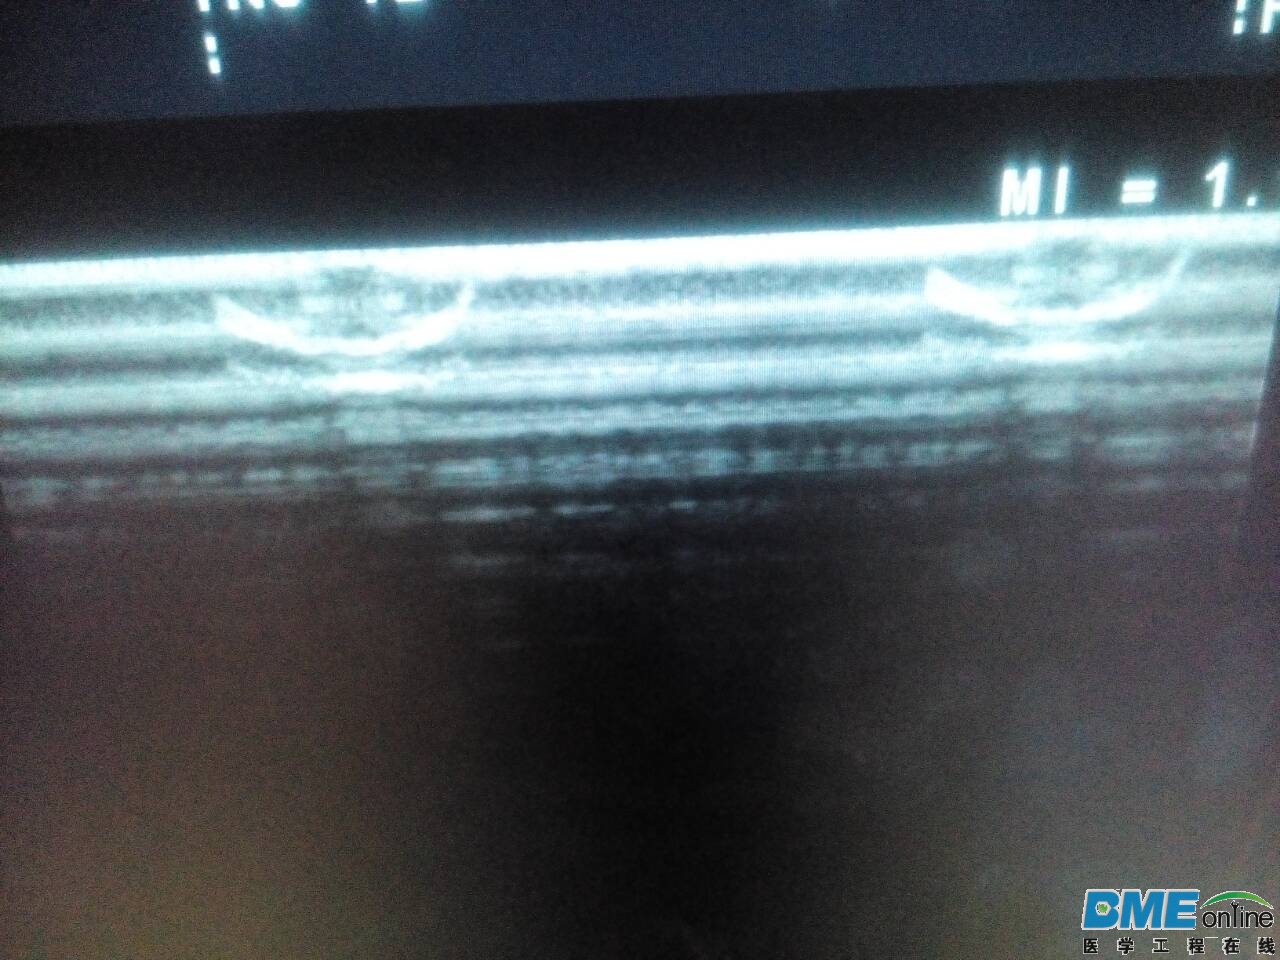

检查图像出现两个对称的的小缺口,切换每个探头都存在。

这应该是阿洛卡的通病,我们这边有台A7,也是类似问题,要换板,

应该是通道板的问题

4950通道板故障,@10的通病。